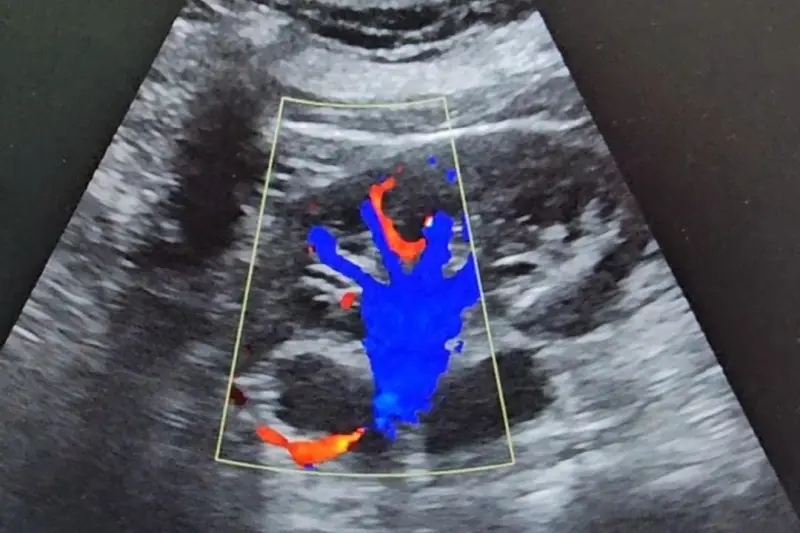

O Hospital Regional de Oriximiná Menino Jesus (HRMJ) vem ampliando o acesso a exames de imagem de alta precisão. Entre os destaques está a ultrassonografia com doppler, tecnologia que combina o ultrassom tradicional à avaliação do fluxo sanguíneo em tempo real, permitindo diagnósticos mais detalhados e seguros.

O exame de ultrassonografia com doppler é um método indolor, não invasivo e sem radiação, com resultados em tempo real. Segundo o médico ultrassonografista Carlos Aleixo, o exame é essencial para analisar o fluxo em vasos sanguíneos.

“O doppler nos permite avaliar a estenose, a circulação arterial e venosa identificando possíveis alterações como trombos (coágulos) e placas de gordura (ateromas) no paciente”, explicou o especialista.